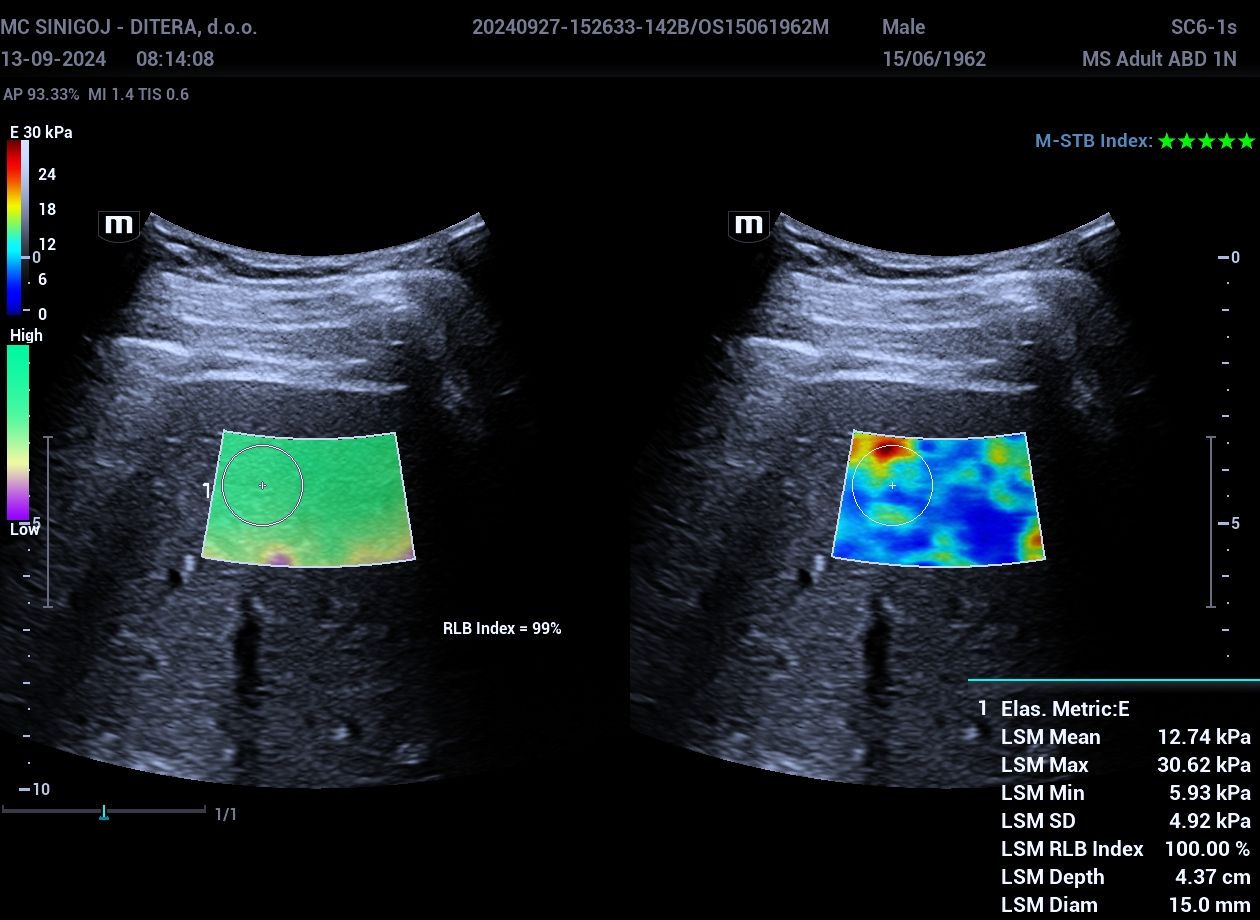

Elastografija in UZ jeter

Kvantitativna ocena elastičnosti jeter (numerična) / Sheare  Wave Elastography

Enote za oceno elastičnosti jetrnega parenhima: kPa ali m/s.

Normalno:  < 5 kPa

Mejno patološko:  5-10 kPa

Patološko:  10-15 kPa

Napredovala kronična bolezen jeter (fibroza, ciroza):  > 15 kPa